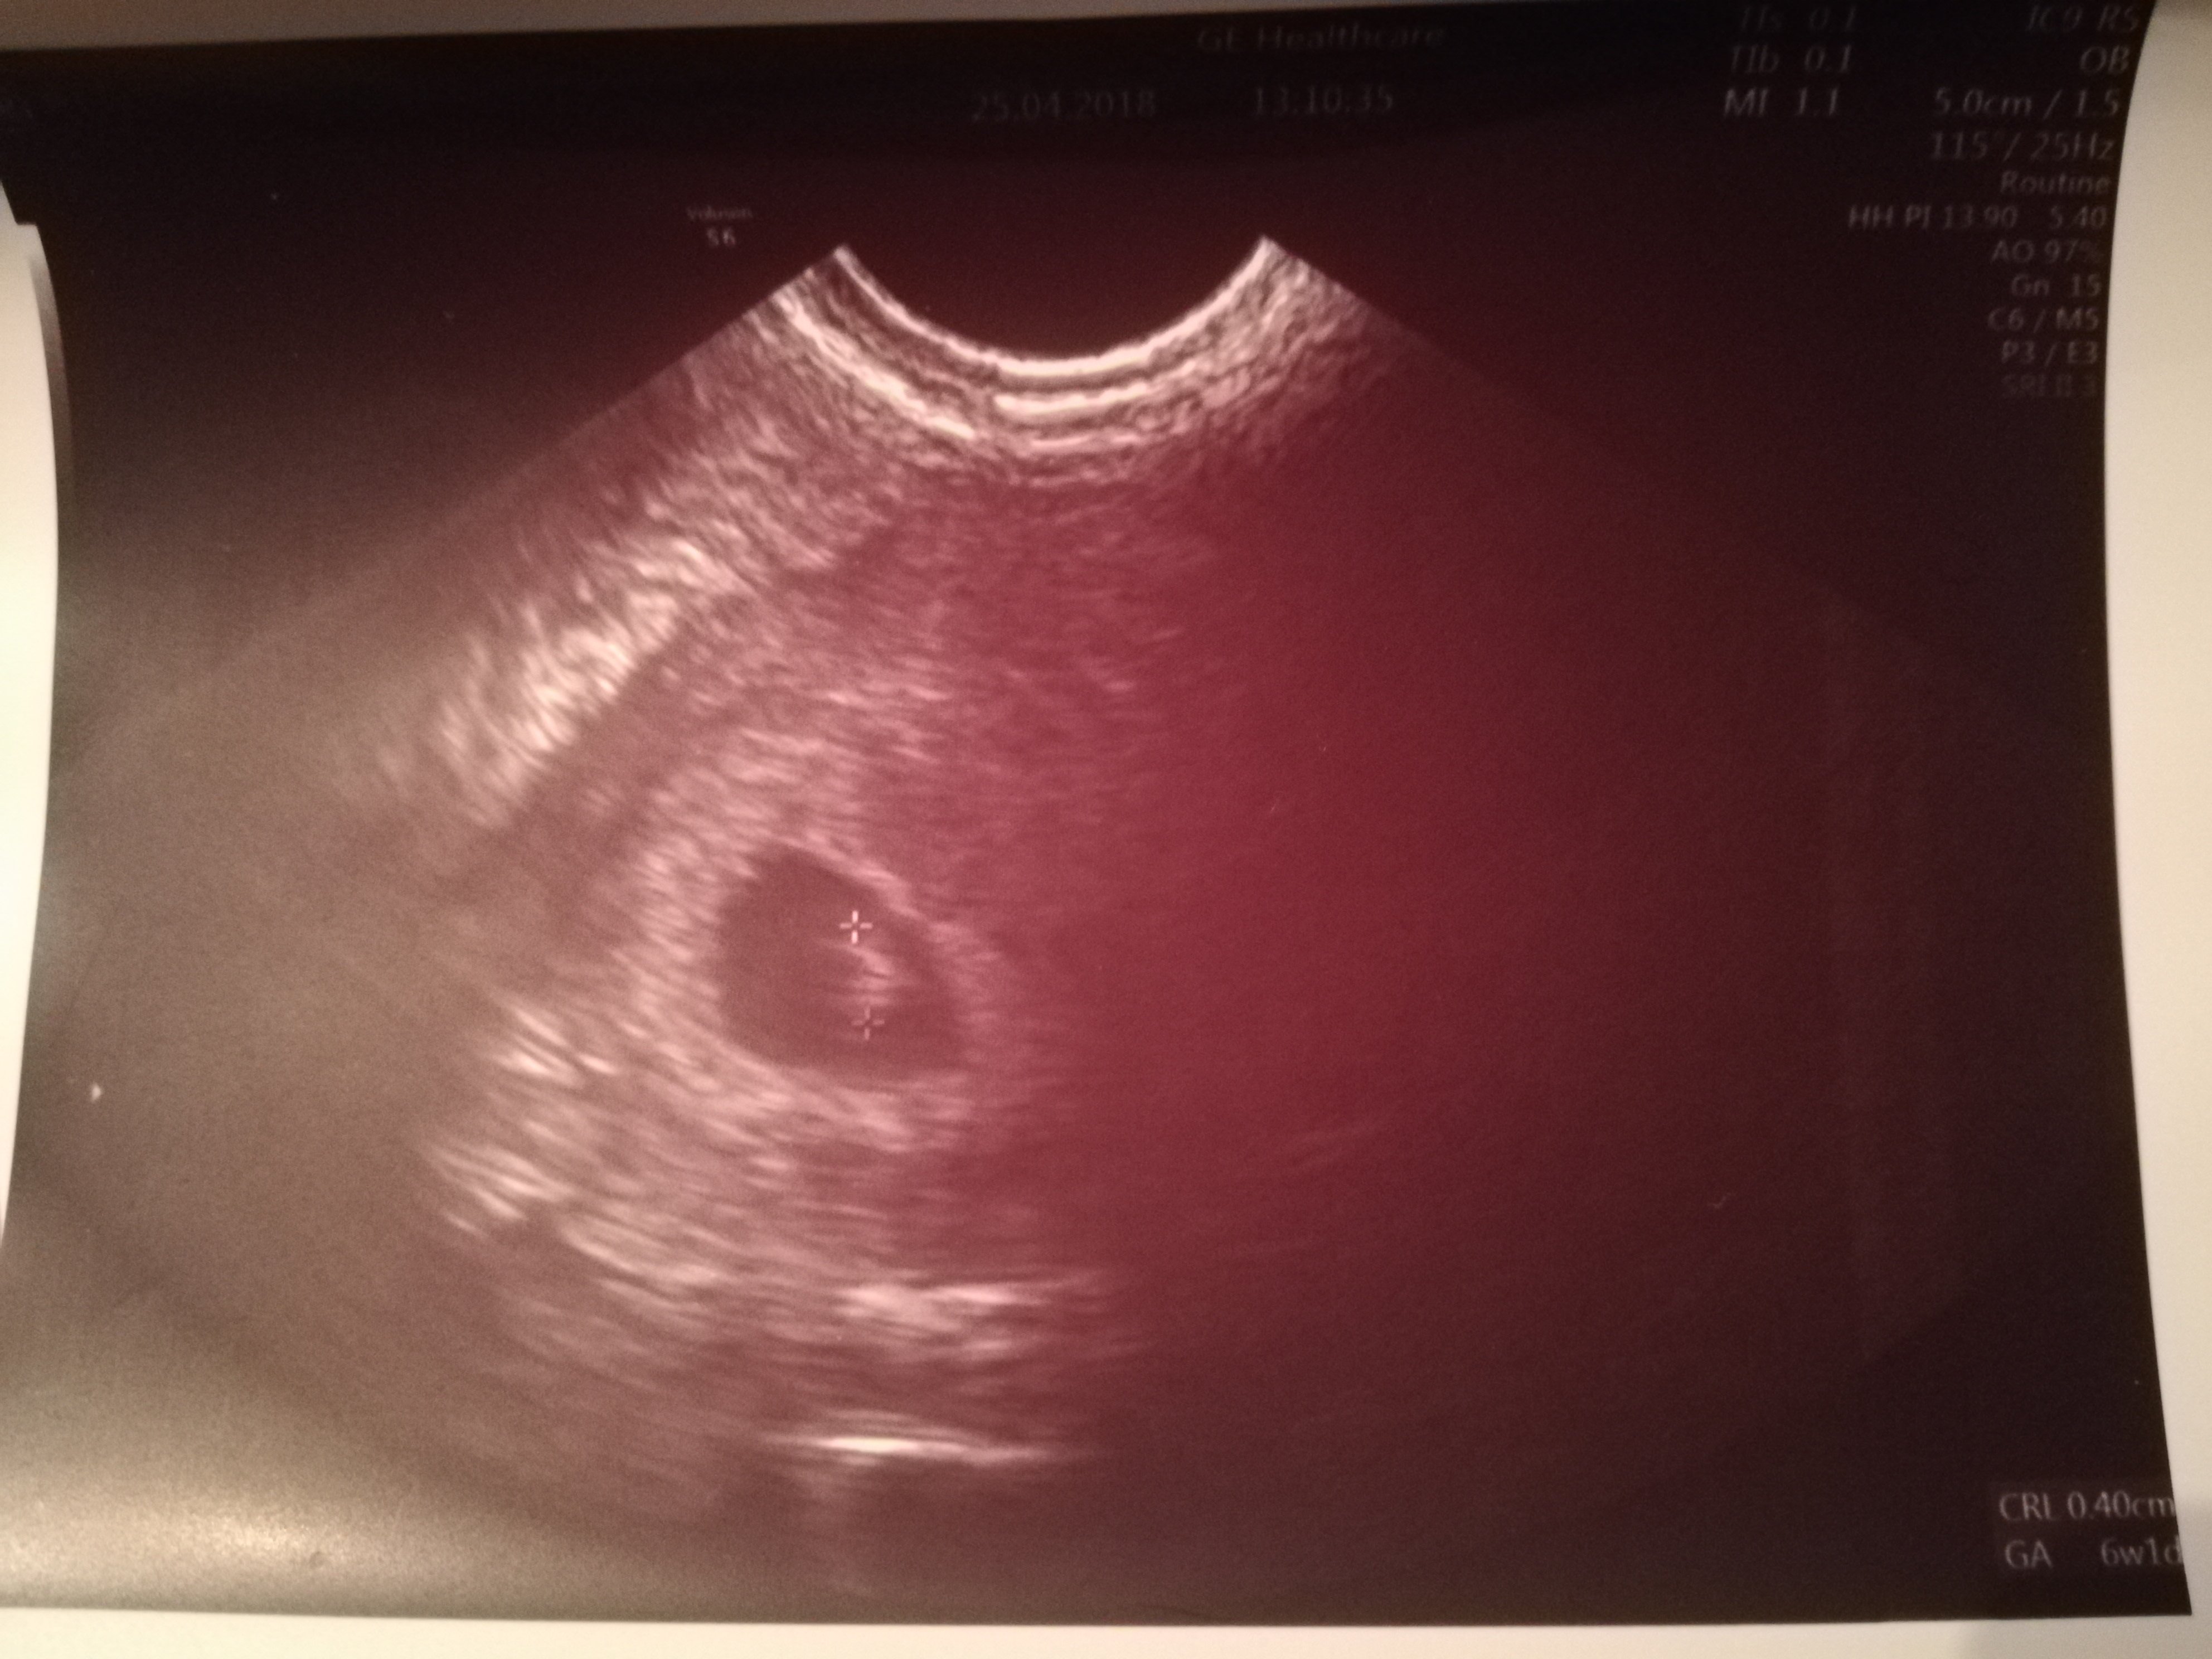

Tamizą suuuper :*29 dpt 3 dniowych zarodków

Najpiękniejszy cud